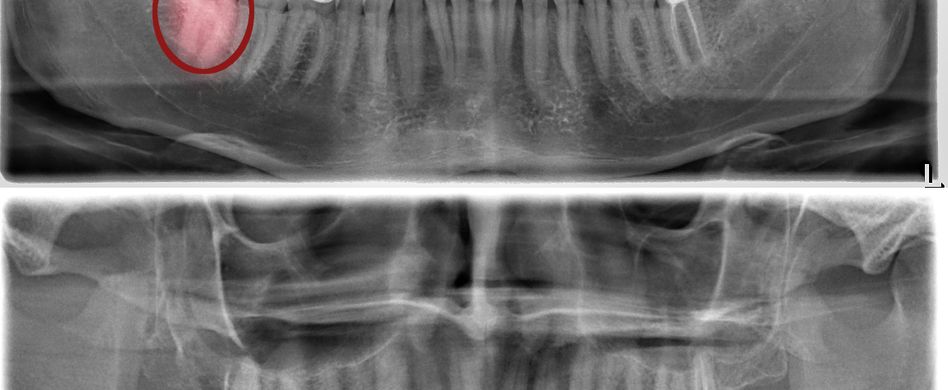

Zahnschmerzen entstehen, wenn aufgrund verschiedener Auslöser die im Zahnmark (Pulpa) befindlichen Nervenfasern gereizt oder angegriffen werden. Eine Entzündung der Zahnpulpa bezeichnen Zahnärzte als Pulpitis. Die Nervenfasern reagieren bereits auf geringste Reize. So werden über freiliegende Zahnhälse Reize über das Zahnbein zum Zahnmark geleitet, da sich das schützende Zahnfleisch zurückgezogen hat. Der Zahn reagiert schmerzempfindlich auf Hitze, Kälte, Saures und Süßes. Zerstören Zahnerkrankungen wie etwa eine Karies die Schutzbarriere, die Zahnschmelz, Zahnzement und Zahnbein bieten, ist der Zahnnerv ungeschützt. Bakterien können eindringen und zu einer Zahnwurzelentzündung bis hin zum Absterben des Zahns führen.

- eine Zahnwurzelentzündung (ausgelöst beispielsweise durch Bakterien oder ein Traumata in Folge eines Stoßes oder Schlags auf den Zahn)

- einen Abszess (Eiteransammlung als Folge einer Zahnwurzelentzündung)